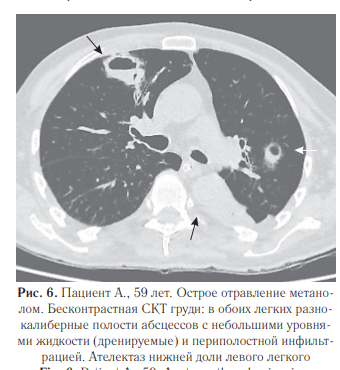

При проведении судебно-медицинской экспертизы выявлены массивные билатеральные гематомы головного мозга (данные аутопсии представлены на рис. 3), а также инфильтративные изменения в легких с полостями абсцессов (рис.10). Исследования легких: при поступлении (рис. 4), рентгенограмма органов грудной полости (рис. 5) и СКТ груди с реконструкциями в динамике через 1 месяц (рис. 6–8).

На рис. 9 представлена рентгенограмма органов грудной полости, выполненная перед смертью пациента. Гистологическая картина по данному случаю отравления. Головной мозг: кровоизлияния (гематомы) с организацией, глиальным рубцом по периферии, с лейкоцитарно-ядерным детритом, слоистым фибрином на фоне эритроцитарных масс; тромбоз некоторых сосудов, кое-где с перифокальным воспалением; фибриноидный некроз стенок отдельных сосудов. Отек головного мозга, местами вплоть до сетчатости, с очагами нейронодистрофии, фокусами выпадения нейронов; прогрессирующий склероз, отек пиальных структур коры головного мозга. Глиальный рубец (в подкорковом отделе), с участками нейронодистрофии, с фокусами кариорексиса, кариолизиса к карнификации; очаговая инфаркт-пневмония (в одном из срезов) с гнойным воспалением, с очагами абсцедирования, местами с признаками организации; полнокровие сосудов с эритро-, лейкостазами, тромбами с фибрином в просветах некоторых сосудов в легких. В сердце: неравномерно-концентрический фиброгиалиноз стенок артериальных сосудов с умеренным сужением просветов отдельных сосудов; периваскулярный, очаговый межуточный сетчатый фиброз; фокусы липоматоза в строме; хаотичное расположение, полиморфизм кардиомиоцитов; фокусы миофрагментации, волнообразной деформации мышечных волокон; неравномерное кровенаполнение сосудов с участками венозно-капиллярной гиперемии.